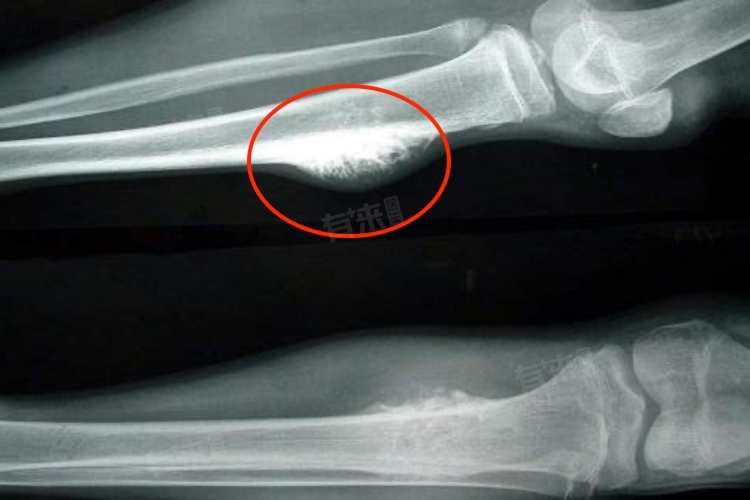

此外,患者还可能在骨骼表面触及硬的肿块,伴随肿胀或关节活动受限。在严重的情况下,骨癌还可能导致病理性骨折,即因骨骼受到肿瘤侵蚀而变得脆弱,从而发生骨折。此外,患者还可能出现发热、体重下降、疲劳等全身症状。因此,患者一旦出现相关症状,应及时就医并接受专业医生的诊断和治疗。